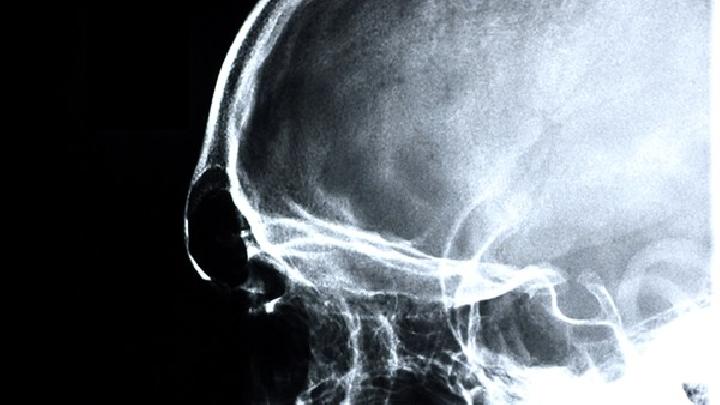

4、心电图、脑电图、脑CT或MRI检查,有诊断与鉴别意义.